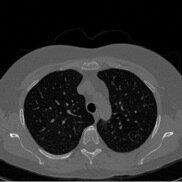

Conditional Samples (Poisson vs Gaussian DPS)

Poisson

Gaussian